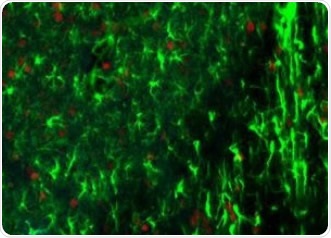

Rodent brain (top) depicting simultaneous acquisition of fluorophores Cy2, Cy3 and Cy5; Brain image (bottom) magnified to 0.5 μm

Figure 1. Rodent brain (top) depicting simultaneous acquisition of fluorophores Cy2, Cy3 and Cy5; Brain image (bottom) magnified to 0.5 μm. Image credit: Huron Digital Pathology.

• This is the only confocal fluorescence digital slide scanner that enables the simultaneous acquisition of up to three fluorophores spanning the whole visible spectrum, from 400nm-850nm. This provides considerable time-savings and less photo bleaching due to the unique flying-spot laser platform.